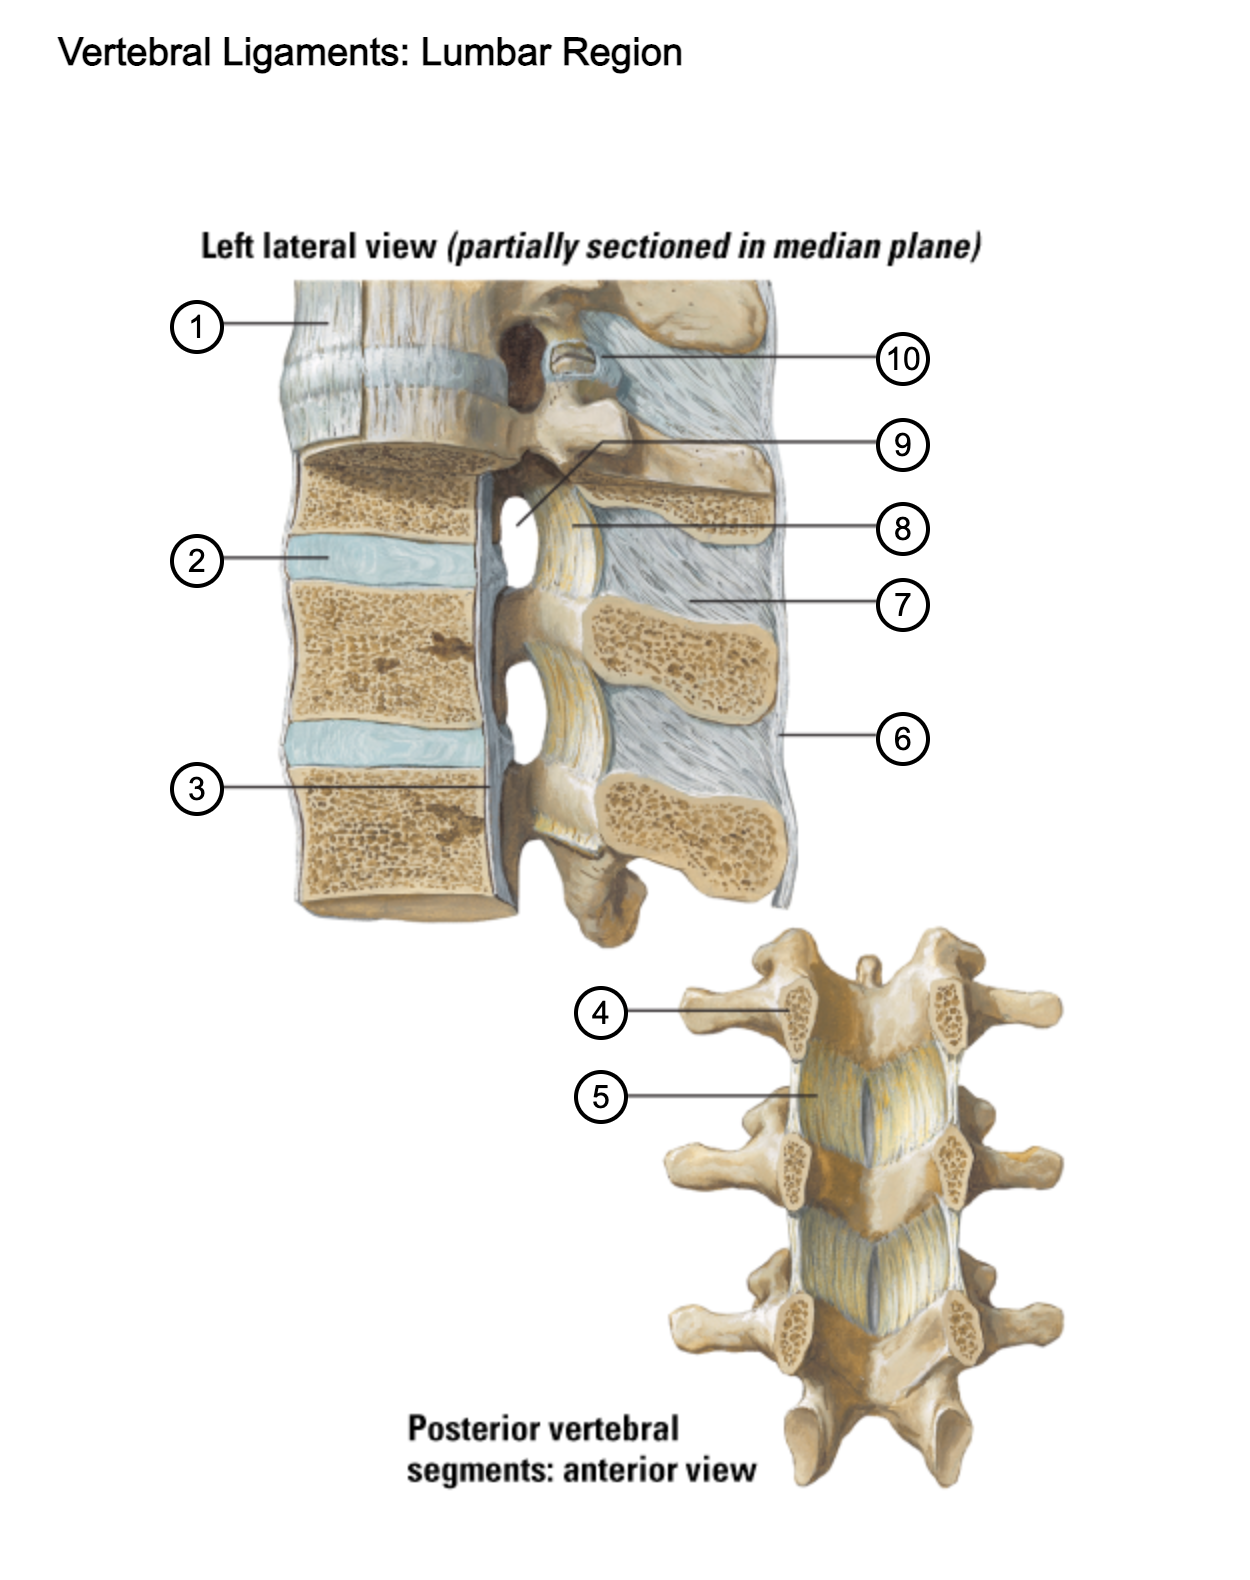

1

anterior longitudinal ligament

2

intervertebral disc

3

posterior longitudinal ligament

4

pedicle (cut surface)

5

ligamentum flavum

6

supraspinous ligament

7

interspinous ligament

8

ligamentum flavum

9

intervertebral foramen

10

capsule of zygapophysial join (partially opened)